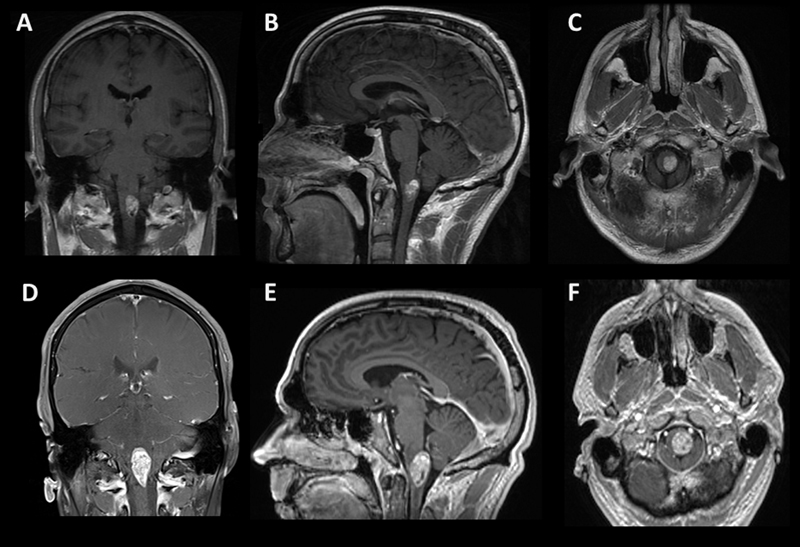

A 38-year-old male with a past medical history of melanoma in situ of the trunk, status post excision, and no family history of cancer, presented with subacute onset of progressively worsening dysesthesia first involving his upper extremities and progressing to affect his right chest and leg over two weeks. MRI of the brain and cervical spine demonstrated a well-localized cystic enhancing anterior medullary-cervical lesion measuring 1.3 x 1.1 x 1.7 cm, with T2 hyperintensity of the lesion and medullary pyramids (Fig.1A, 1B, 1C). He was admitted to the neurology service for an expedited evaluation of infectious, rheumatologic, neoplastic, and inflammatory etiologies. MRI of the spine and whole-body PET/CT revealed no other lesions. Serum studies were unremarkable, and lumbar CSF contained 1 WBC, 3 RBC, glucose 55, protein 57 (ref 15-45), no oligoclonal bands and negative infectious studies, flow cytometry, and cytopathology. He was treated with high dose IV methylprednisolone for five days and discharged home on a steroid taper. He had progression of symptoms, and a repeat MRI two months later showed growth of the lesion to 3.3 x 1.7 x 1.5 cm (Fig.1D, 1E, 1F). Subsequently, he underwent a suboccipital C1 laminectomy and subtotal surgical resection of the mass.

Figure 1. Radiographic findings. Coronal (A, D), sagittal (B, E), axial (C, F) post-contrast T1 MRI of the brain. The top row (A-C) shows MRI imaging of the brain at presentation, and the bottom row (D-F) is two months later before tumor resection.

Although non-specific, MRI of astroblastomas have been described to enhance, as well as appear well-demarcated, cystic, and lobulated, which is consistent with our case and similar to other cases of EWSR1-BEND2 fused astroblastoma tumors (Fig.1).3,4,6 Comparable to conventional MN1-altered astroblastomas and other cases of EWSR1-BEND2 fused tumors, our case showed perivascular growth and immunohistochemistry was positive for S100, OLIG2, EMA and GFAP.2–4 Ultrastructural observations in astroblastomas suggest a relationship to tanycytes, an ependymal cell subtype, but it is unclear if this applies also to MN1-altered and EWSR1-BEND2 fused astroblastomas.1,2

Given the rarity of these tumors, there is no defined standard established treatment. Based on studies of non-molecularly characterized astroblastoma, resection remains the cornerstone of therapy to improve outcomes, as supported by an analysis of 116 patients that found that gross total resection improved outcome with a 5-year progression-free survival of 83% versus 55% in those with subtotal resection.1 Regarding radiation, a systemic review of 95 histologic astroblastoma patients did not show a survival benefit with radiation therapy; however, the series had a broad age range from 1 to over 61 years of age and did not compare survival differences in astroblastoma with and without anaplastic features.14 Review of the literature found that a 20-year-old woman with a spinal cord MN1-altered astroblastoma, and a 36-year-old man with a spinal astroblastoma with EWSR1-BEND2 both had a reduction in tumor size after radiation, temozolomide, and bevacizumab.4,15 In another case, a 3-month old boy with EWSR1-BEND2 astroblastoma had progressive disease after five days of temozolomide and etoposide.3 Given the significant growth of the presented patient's tumor in two months (Fig.1) and dramatically elevated Ki67 proliferation index, he was treated with concurrent radiation with temozolomide followed by adjuvant temozolomide based on the “Stupp” protocol and this appears to be a viable option, as he has had a partial response control of his tumor over one year later at the time of writing.16